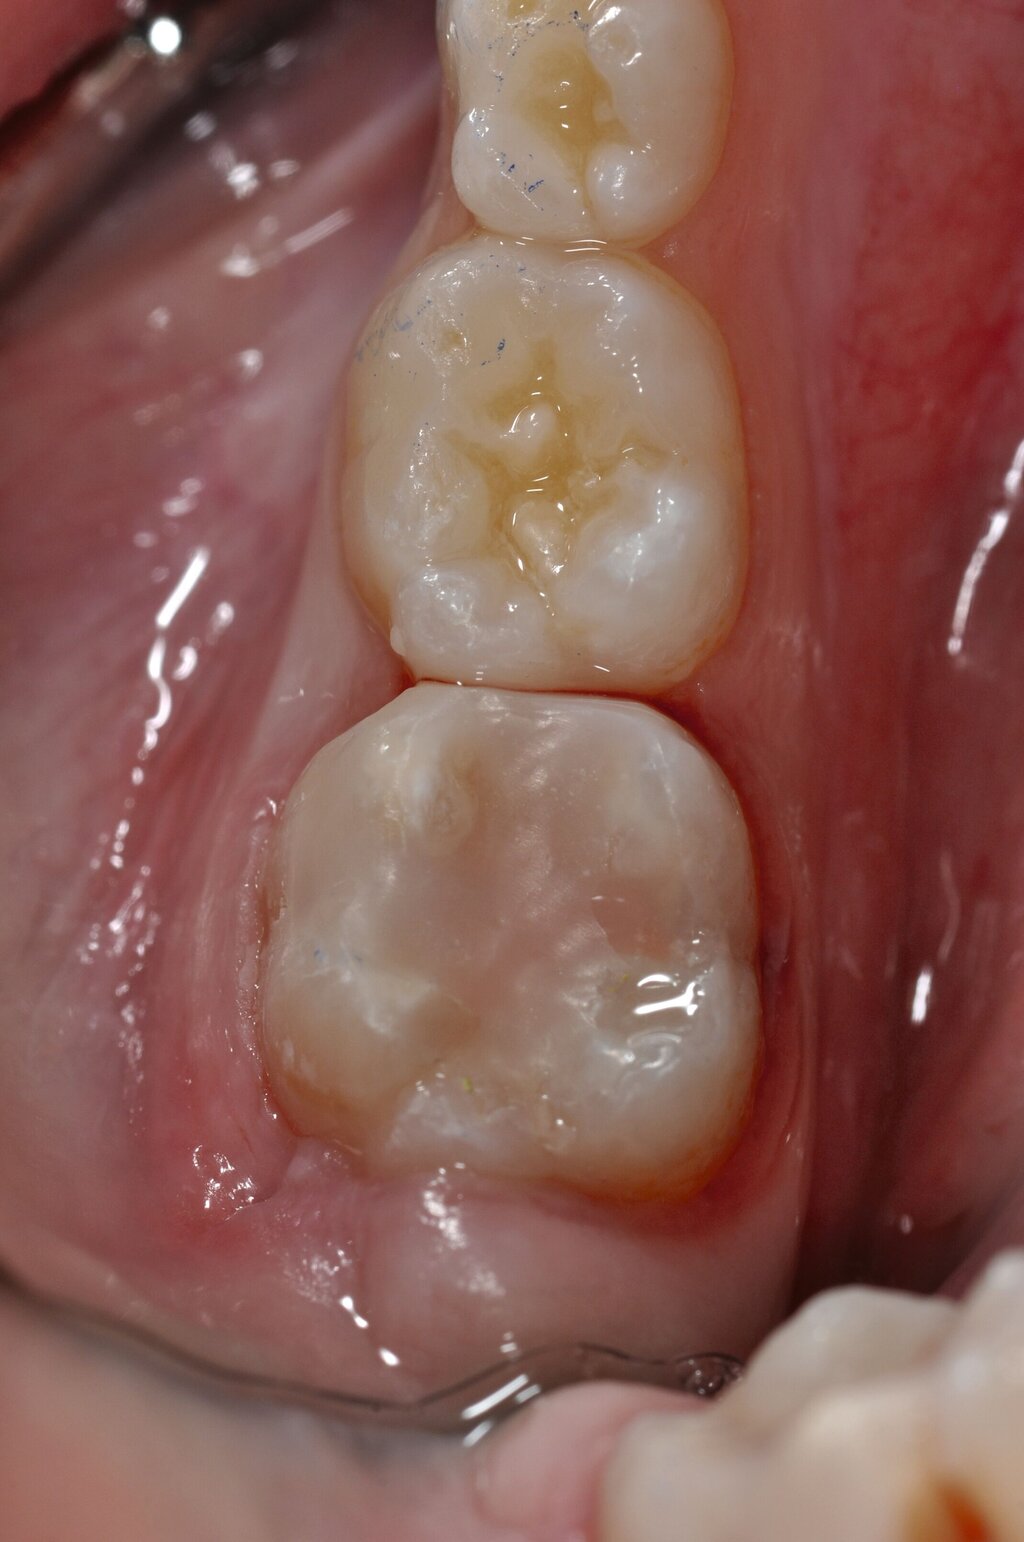

Die „temporäre Therapie“ umfasst neben den konfektionierten Edelstahlkronen (Abbildung 6) [Kotsanos et al., 2005; Oh et al., 2020] nun auch die vorgefertigten Zirkonoxidkronen [Geduk et al., 2023; Talekar et al., 2023]. Stahlkronen (SSC, stainless steel crowns; PMC, preformed metal crowns) werden heute auch mittels Halltechnik eingesetzt [Grizzo et al., 2022].

Vorteil ist dabei, dass aufgrund der geringen Schichtstärke der Kronen keine Zahnhartsubstanz geopfert werden muss. Die Indikation zum Einsatz dieses Verfahrens ist eine mittelfristige Versorgung über wenige Jahre, wenn beispielsweise der optimale Zeitpunkt für die Extraktion abgewartet werden muss. De Farias et al. konnten zeigen, dass über einen Zeitraum von 24 Monaten eine Versorgung von MIH-Molaren mit Stahlkronen eine signifikant höhere Überlebensrate aufwies als die Kompositversorgung [de Farias et al., 2022].